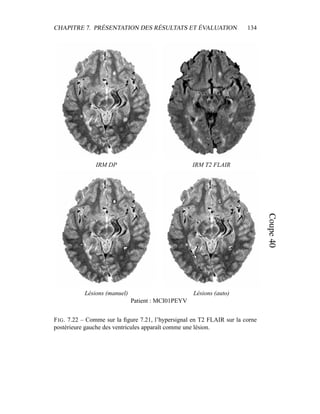

c’est donc sur elle que portera l’analyse lors de la segmentation en tissus et de la

présentation du modèle de volume partiel. Les autres modalités seront utilisées a

posteriori.

4.4 Segmentation en tissus.

4.4.1 Algorithme

Le but de cette segmentation en tissus sains est leur caractérisation, afin de

pouvoir construire un premier processus de détection des lésions de SEP. Même

si les 4 séquences (T2 FSE / DP, T1, T2 FLAIR) sont disponibles, la segmenta-

tion ne sera menée dans un premier temps que sur le couple T2/DP, alors que les

autres séquences – T1, T2 FLAIR – montreront tout leur intérêt pour la détection

des lésions et leur spécification : ceci permet de n’effectuer la segmentation que

sur des images vierges de tout rééchantillonnage. En outre, nous ferons délibéré-

ment l’impasse sur certains processus décrits dans la littérature pour améliorer la

qualité visuelle de la segmentation – les contraintes sur le voisinage, par exemple

– puisque notre but est d’obtenir un critère sur l’intensité qui sera raffiné ensuite

par contraintes spatiales.

Dans sa formulation la plus simple, le processus de segmentation prend un

ensemble multi-séquences à segmenter – les deux images T2 / densité de pro-

tons, auxquelles le masque binaire du cerveau a été appliqué – et fournit en sortie

3 labélisations : matière blanche, matière grise, LCR. Comme indiqué dans les

CHAPITRE 4. SEGMENTATION EN TISSUS 53

équations 4.10 et 4.11, l’algorithme EM donne deux grands résultats :

– la labélisation des segmentations via les γk

i

– l’estimation des paramètres du modèle µk et Σk.

4.4.2 Présentation des résultats

Pour éliminer dans un premier temps l’influence des lésions de SEP, un témoin

a été choisi pour cet exemple, et les résultats sont présentés dans la figure 4.5. Pour

la segmentation du masque du cerveau, seule la segmentation était intéressante.

Une mauvaise estimation des paramètres de classes, ou un mauvais modèle était

sans importance tant que la segmentation était valide. Par contre, dans le cas de la

segmentation en tissus, avoir une bonne estimation des paramètres est primordial,

car c’est à partir de là que les lésions de SEP vont être segmentées. Pour obser-

ver la qualité de la segmentation dans la figure 4.5, il faut donc en permanence

regarder deux espaces reliés.

– L’espace des intensités : visualisé via l’histogramme conjoint entre les deux

modalités, il est représenté par les paramètres de classes µk et Σk. Une mé-

thode pour visualiser ces paramètres est de tracer l’estimateur de confiance

donné par p(Z = z) = cte. Dans un espace 2D, cet estimateur est en fait

l’ellipse de Mahalanobis donné par 1

2

(X − µk)T

Σ−1

k (X − µk) = λ. Dans

toutes les figures similaires à la figure 4.5, les ellipses vérifieront λ = 1.

Pour avoir une meilleur visibilité de l’histogramme, celui-ci est en fait un

log-histogramme : la couleur de chaque pixel de l’image correspond au log

du nombre d’occurences du couple (IT2, IDP ) correspondant dans le couple

d’image IRM T2 / IRM DP. Ceci permet essentiellement de visualiser sur

le même histogramme le LCR avec le reste des tissus, bien que le nombre

de voxels correspondant au LCR soit très faible.

– L’espace des images, dans lequel les segmentations sont effectivement vi-